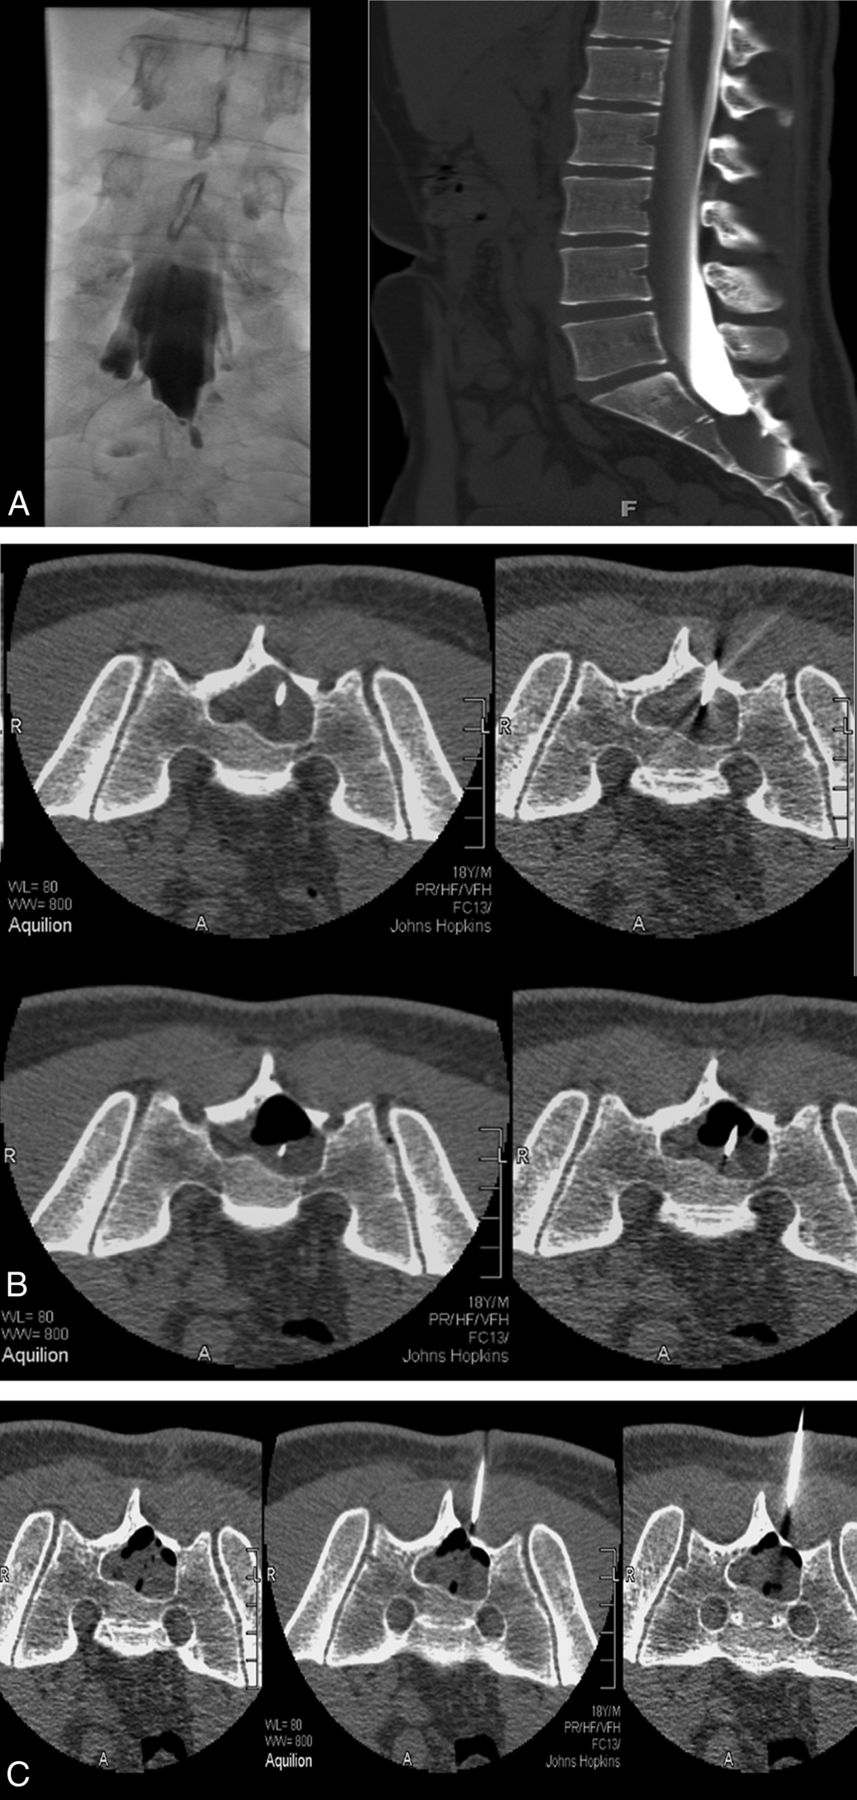

All patients included in our cohort were treated by using the aspiration-injection technique previously described by Murphy et al.36 Briefly, aspiration was preceded by performance of diagnostic CT (Aquilion 16-detector row multidetector CT unit; Toshiba Medical Systems, Tokyo, Japan) to select the level providing access to the cyst through the thinnest overlying bone. Sedation was induced intravenously. The back was prepared in the usual sterile fashion, with local anesthesia infiltrated into the skin, fat, muscles, and periosteum overlying the sacrum. Two 18-ga needles were advanced into the cyst with CT fluoroscopy (13 frames per second, 3 adjacent 2-, 4-, and 2-mm sections) (Fig 2). The tip of the first needle was typically placed deep in the cyst, while the second was placed more superficially. The stylets were removed from both needles, and fluid was aspirated via the deeper needle. The more superficial needle served as a venting tube during the aspiration process, allowing air to enter the cyst. Following aspiration, an air-fluid level developed; this was monitored intermittently with CT fluoroscopy for evidence of rapid cyst refilling, which would indicate a connection to the thecal sac. (We avoided using iodinated contrast agents to monitor cyst fluid levels because these fill up the cyst, complicate fibrin injection, and impair fibrin binding while providing no appreciable additional information compared with air-fluid levels). A commercially available fibrin sealant composed of human/bovine fibrin, fibrinolysis inhibitor, thrombin, and calcium chloride was next injected into the cyst through the deep needle (Tisseel VH; Baxter Healthcare, Deerfield, Illinois).

A, CT myelogram and myelogram showing minimal filling of a large right S2 Tarlov cyst with a narrow neck. There is significant remodelling of S2 and S3. B, With 18-ga spinal needles in place, one deeper than the other, partial aspiration has developed an air-fluid level. C, Injection of fibrin fills the cyst 80%. The volume of fibrin injected is close to the volume of CSF aspirated.

Following our observation that completely filling cysts with sealant often temporarily exacerbated postprocedural radicular pain (likely due to swelling sealant compressing the affected nerve root or nearby nociceptors), we adjusted the technique so that sealant injection was halted when CT fluoroscopy indicated that the cavity was approximately 75% full rather than 100% full. This step was found to address the postoperative pain issue without compromising efficacy. Both needles were then withdrawn, and the puncture sites were covered with an antibiotic ointment and a sterile dressing. Patients were observed for 2 hours after the completion of the procedure before being discharged. They were asked to stay locally for 1 night and were permitted to return to their normal physical activity immediately but were advised not to undertake strenuous physical exercise for 2–3 weeks. If multiple cysts were present, typically only 2 were treated per session, so some patients returned for repeat sessions.